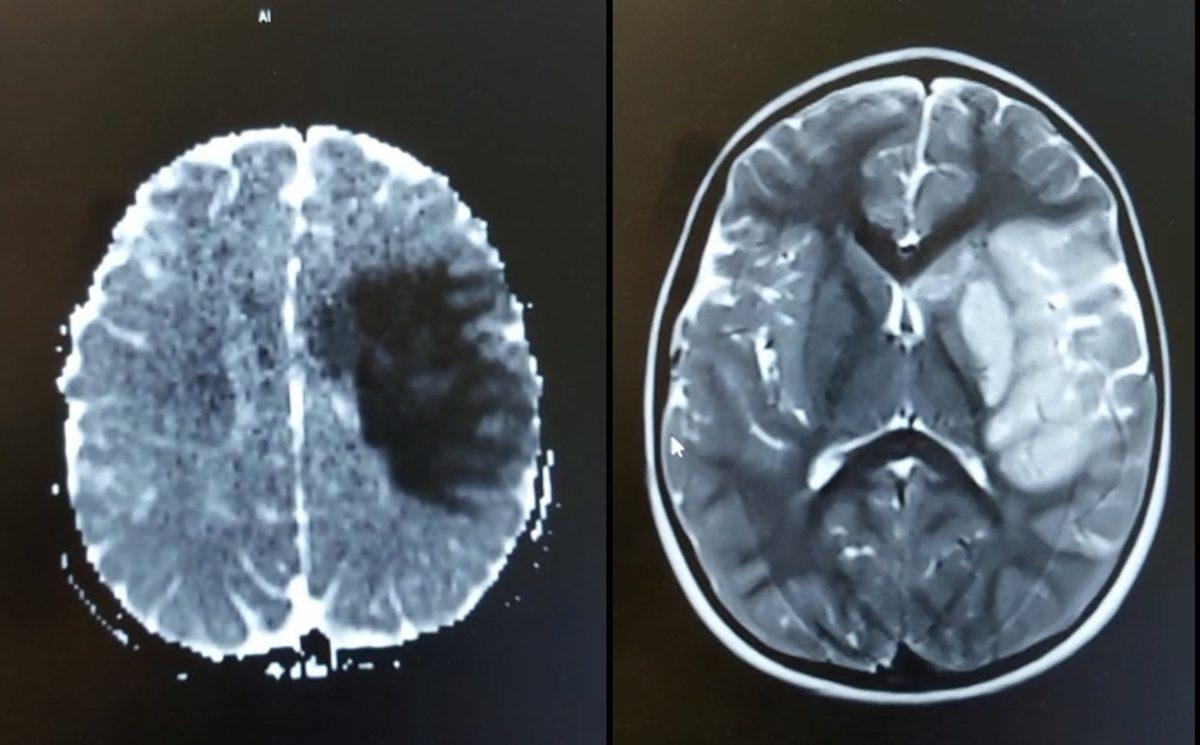

4 yaşındaki bir kız çocuğu. COVID-19'a bağlı beyin orta arter tıkanması nedeniyle sağ tarafı felç olmuş. Yoğun tedavi görmesine rağmen çok az bir düzelme var.

Üstelik kronik hastalığı yok, hastalık öncesinde tamamen sağlıklı.